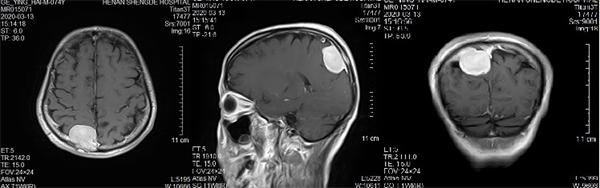

映象网信阳讯(记者 吴彦飞 通讯员 吴琼 曹启合)日前,74岁的葛大爷,因“发作性头晕5年”,在居住当地医院行颅脑MRI(核磁共振)提示颅内占位。紧急转入河南圣德医院神经外科,行MRI提示:矢状窦旁脑膜瘤。

入院后河南圣德医院副院长兼神经外科主任于耀宇查看患者病情,告知其家属脑肿瘤直径较大,压迫功能区,且与上矢状窦粘连,占位效应明显,有明确手术指征,但手术风险较大,手术过程有可能造成上矢状窦大出血及部分神经功能缺失,家属商量后同意手术。

术前核磁共振检查